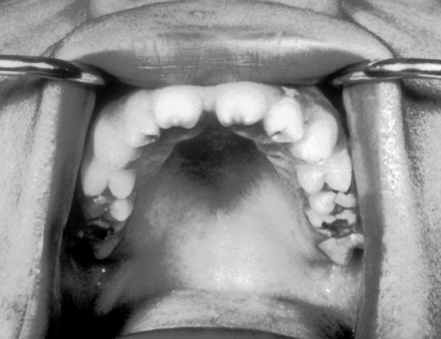

- Hutchinson’s teeth

- High-arched palate

- Short maxilla